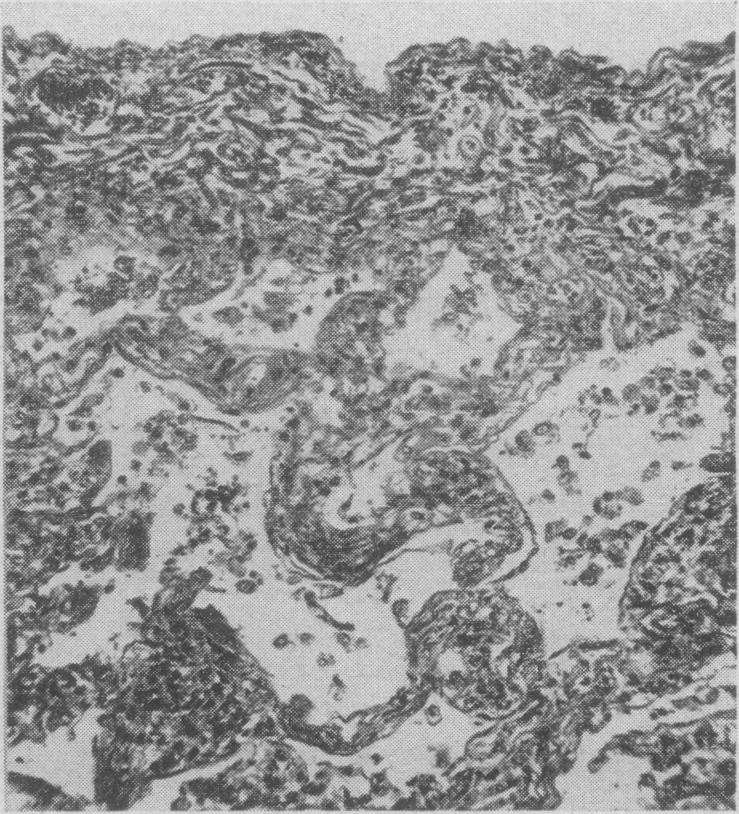

Pulmonary complications during treatment with hexamethonium.

Can Med Assoc J. 1955 Mar 15;72(6):448-51.